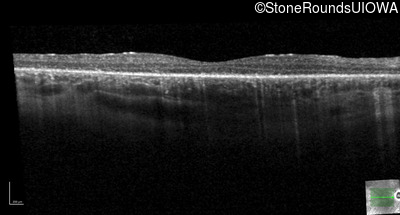

Optical Coherence Tomography - Left - 20/50

Exemplar / OCT Stack

OCT Stack